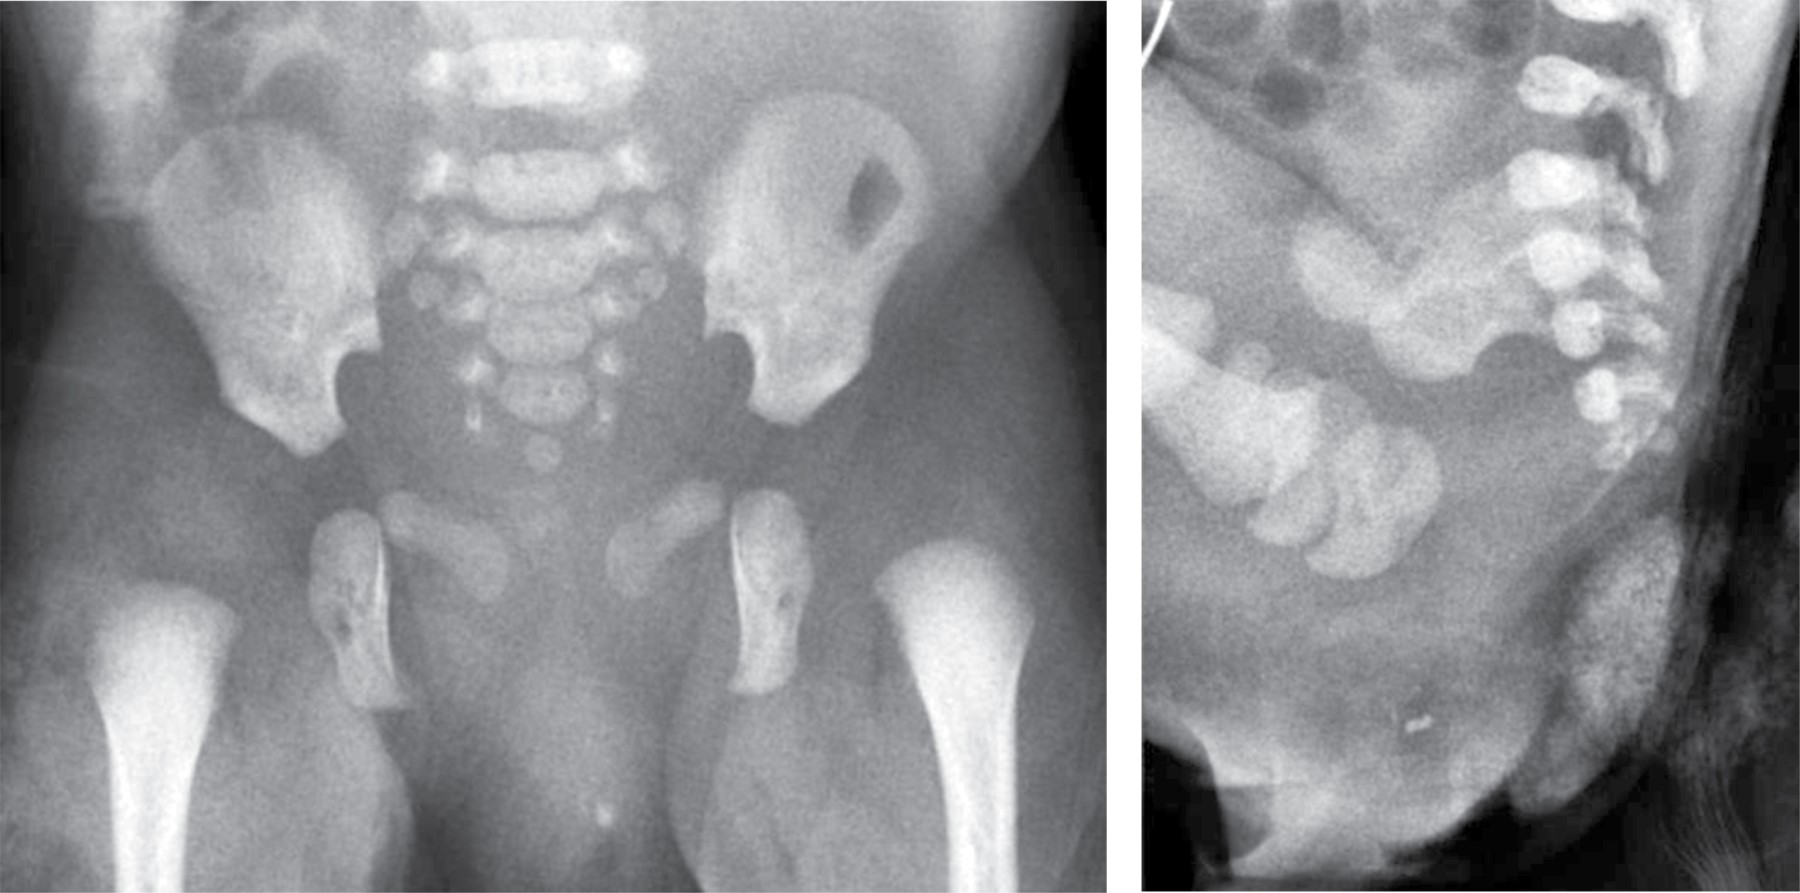

El abordaje diagnóstico imagenológico es esencial para demostrar la extensión intraabdominal y los efectos en las estructuras adyacentes. Los hallazgos por imagen del teratoma van acordes a sus componentes. Por radiografía se observará una masa de dimensiones variables que puede estar asociada a calcificaciones.10 El ultrasonido mostrará una masa de ecotextura heterogénea con presencia de focos ecogénicos de calcificaciones y grasa así como áreas quísticas anecoicas. El modo Doppler color demuestra que los componentes sólidos presentan vascularidad de moderada a alta.10,11 La tomografía computarizada muestra una masa con densidad heterogénea por sus componentes de grasa, calcio, tejidos blandos y niveles de líquido. El medio de contraste muestra un patrón de reforzamiento variable en los componentes sólidos. La resonancia magnética presenta hallazgos con intensidad de señal heterogénea. En T1 la grasa se aprecia hiperintensa, los tejidos blandos isointensos, el componente quístico hipointenso y el calcio marcadamente hiperintenso. En T2 se observa el componente quístico hiperintenso y el calcio marcadamente hipointenso. El T1 con contraste presenta un reforzamiento heterogéneo del componente sólido.3,10 Los hallazgos por imagen no pueden predecir subtipos histológicos de tumores, pero existen características de benignidad y malignidad. El componente quístico, las calcificaciones y el contenido graso prominente corresponden a hallazgos más comúnmente observados en lesiones benignas. La hemorragia y/o necrosis dentro de la masa, mayor componente sólido y realce heterogéneo con contraste son más sugestivos de malignidad.3,6 El diagnóstico prenatal se realiza con ultrasonido obstétrico y/o con resonancia magnética fetal, identificando una masa sacra heterogénea con componentes quísticos y sólidos.2,3 Postnatalmente la resonancia magnética permite la diferenciación de tejidos, extensión intramedular y pélvica, siendo superior a la tomografía computarizada al no exponer a una dosis de radiación ionizante.12 Se debe realizar diagnóstico diferencial principalmente con mielomeningocele, lipomas, hemangiomas, quiste pilonidal y epidermoide.2,7 El neonato puede presentar complicaciones cardiacas, anemia e hidrops fetal. Durante el parto puede ocurrir ruptura del teratoma y hemorragia al ser altamente vascular. Si es suficientemente grande puede ocasionar efecto de masa en estructuras adyacentes.2,3,13 El tratamiento es principalmente quirúrgico, ya sea prenatal o postnatal. La cirugía fetal intrauterina es una opción en fetos de alto riesgo como los productos con hidrops fetal. Postnatalmente la resección quirúrgica temprana se realiza para evitar progresión a malignidad y recurrencias. Los pacientes con teratoma maligno requieren manejo combinado de cirugía, quimioterapia y radiación.3,14

Paciente femenino de 32 años de edad sin antecedentes de importancia. Tomó ácido fólico previo al embarazo. Gesta dos, cesárea uno. Su primera consulta del embarazo actual fue a las 7.2 semanas de gestación (SDG) con longitud cráneo caudal acorde a la edad gestacional estimada por fecha de última menstruación. En la semana 12 se realizó ultrasonido estructural donde se observó aparente defecto a nivel sacro que parecía tener continuidad con médula espinal. En el ultrasonido a la semana 16 se apreció una imagen de contenido anecoico en la región sacra y con aparente continuidad al canal medular, en probable relación con mielomeningocele (Figura 1). En la semana 20 se realizó amniocentesis y posteriormente microarreglos encontrando complemento cromosómico 46 XX, sin alteraciones en las regiones analizadas. Se realizó tamiz de glucosa y curva de tolerancia a la glucosa en la semana 27 diagnosticando diabetes gestacional, sólo requirió manejo dietético. En la semana 26 se realizó ultrasonido identificando en región glútea una imagen con ecotextura heterogénea de predominio anecoico, con medidas aproximadas de 3.3 × 3.2 cm, que no comprometía genitales y parecía corresponder a un teratoma sacro. Se realizan seguimientos ultrasonográficos con Doppler fetal y pruebas de bienestar fetal hasta el término. A las 38.2 SDG nace por cesárea producto femenino con peso de 2,669 g y talla de 48 cm. Llora y respira al nacer, se dan maniobras básicas de reanimación. Se califica con APGAR 9/9 y Silverman Anderson de 0. Ingresa a terapia intermedia. En la exploración física neurológicamente no mostró alteraciones, la fuerza y sensibilidad de las extremidades estaba conservada, sin movimientos anormales. En la región sacra se identificó una masa con tamaño aproximado de 2 × 2.5 cm que presentó sangrado en capa, la cual de forma atípica no tenía una cobertura de piel (Figura 2). Se realizó radiografía de pelvis, ultrasonido abdominal, transfontanelar y de región sacra. Se tomó radiografía anteroposterior y lateral de pelvis que reveló integridad de los cuerpos sacros y los elementos del arco posterior sin alteraciones aparentes así como una masa con densidad de tejidos blandos inferior a la región del sacro (Figura 3). En el ultrasonido abdominal no se reportaron alteraciones, se valoró la vejiga y riñones, mismos que mostraron situación, morfología y ecogenicidad normales. El ultrasonido transfontanelar no mostró anomalías. Se realizó rastreo con transductor lineal multifrecuencia en escala de grises y con modo Doppler color de la columna lumbosacra (Figura 4). Se decidió realizar resonancia magnética para mejor caracterización de la extensión de la masa descrita. Se efectuaron secuencias multiplanares de la columna lumbosacra y panorámica sagital de la columna completa (Figura 5). Se realiza la resección completa de la tumoración, respetando estructuras pélvicas y lográndose una cobertura completa sin tensión de la herida. Adecuada recuperación postoperatoria, por dehiscencia parcial de herida se maneja sistema VAC ambulatorio, el cual es una terapia no invasiva que utiliza presión negativa sobre la herida para ayudar a la cicatrización en un medio húmedo y cerrado, lo que favorece la angiogénesis, el tejido de granulación y disminuye la colonización bacteriana (Figura 6). Niveles séricos de alfa fetoproteína y fracción beta de gonadotropina coriónica preoperatorios normales. El reporte de patología reveló teratoma inmaduro (elementos inmaduros menores de 1%), superficie externa con piel ulcerada. Después de un año de vigilancia, no hay datos de recidiva clínica o por laboratorio.

Es importante hacer el diagnóstico diferencial con el mielomeningocele, lipomas, hemangiomas, quiste pilonidal y epidermoide.3 Éstos tienen una localización posterior al sacro. El teratoma sacrococcígeo tiene una localización entre el coxis y el ano y tiende a estar recubierto por piel.2 Asimismo, se debe evaluar la médula espinal, dado que el mielomeningocele tiene afectación asociada de la misma.11 En este caso se constató la integridad de los cuerpos sacros y del arco posterior así como del canal medular mediante la valoración con radiografías, ultrasonido y resonancia magnética.